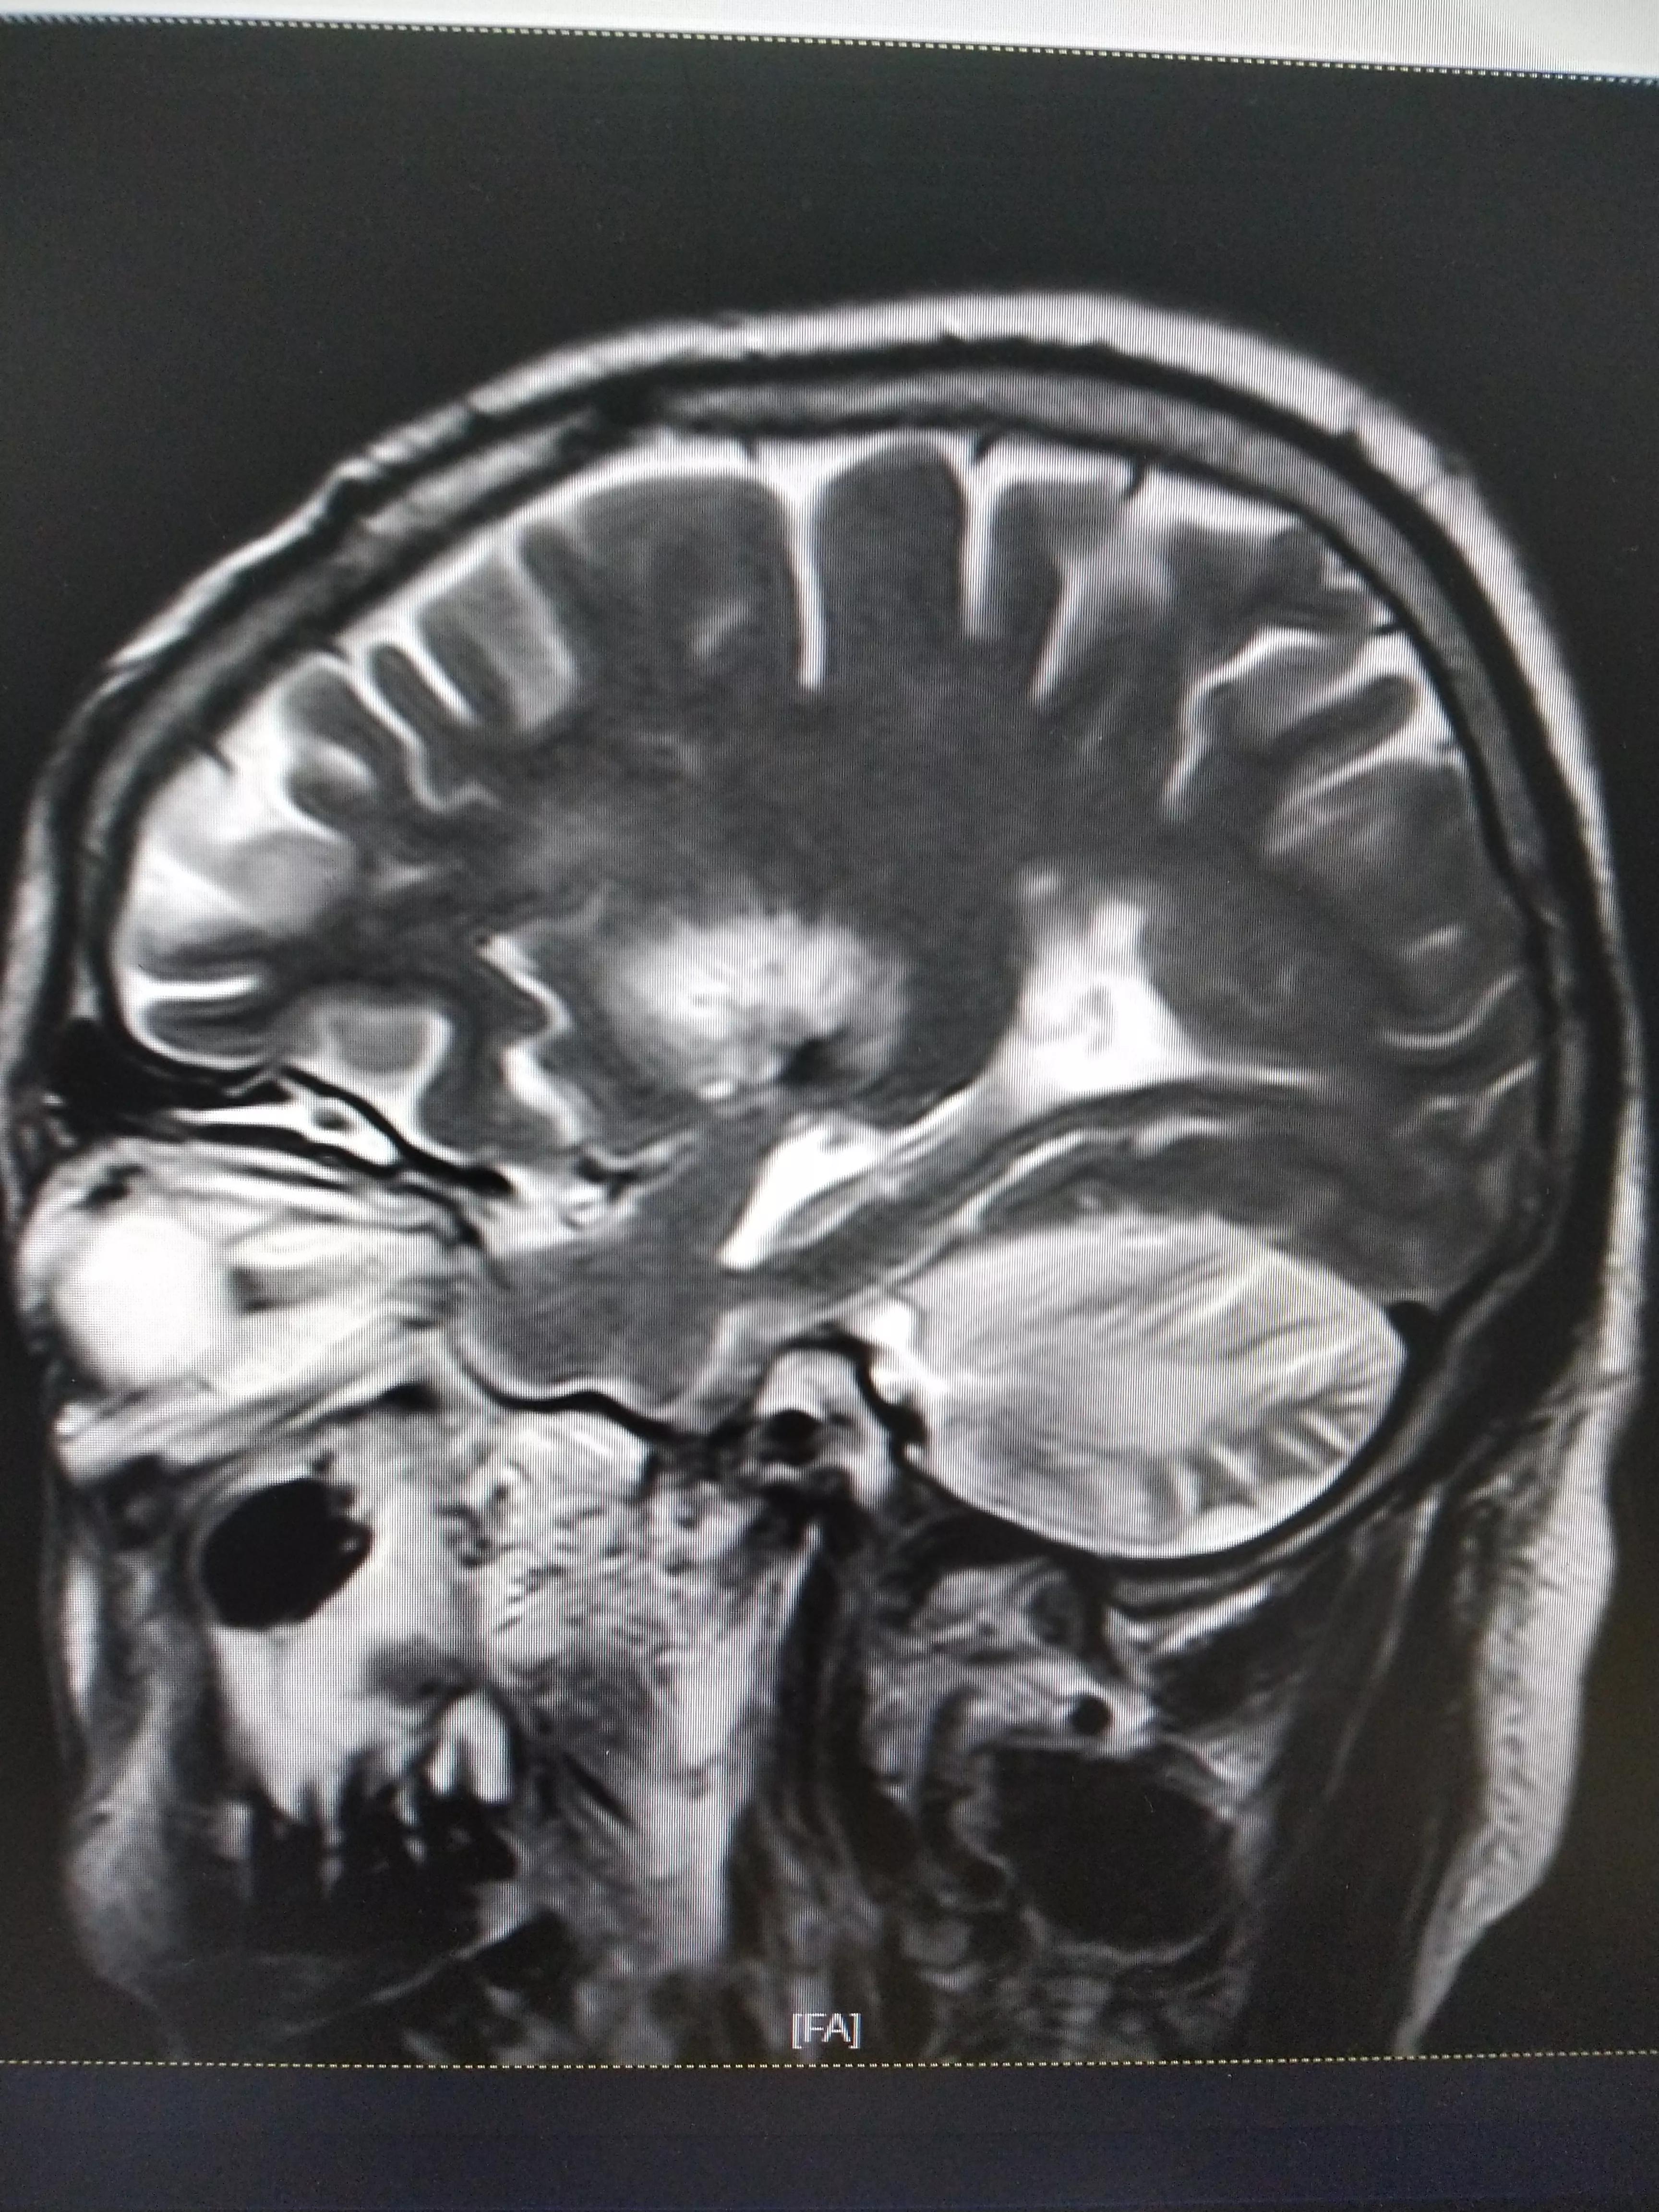

七,昏迷一年后复查颅脑核磁MR

1,脑干出血后,多发性软化灶2,双侧,额叶,顶叶基底节多发脑梗/腔隙性脑梗死。

3,双侧额叶,顶叶,基底节。异常信号考虑胶质增生可能。

4,脑积水。

5,脑萎缩脑白质病变(DWML1级,PVH1级)。